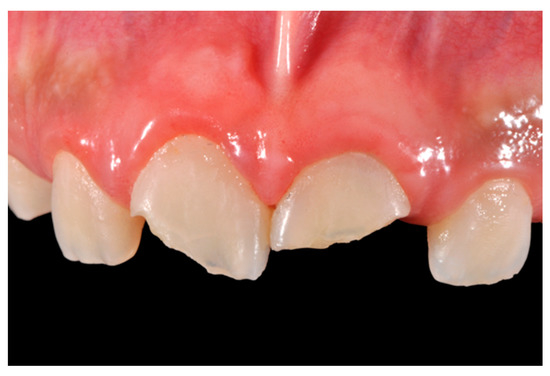

A 27-years lady presented to the dental office after traumatic accident (Figure 30). Tooth #1.1 responded positively to pulp tests (cold and electrical) while Tooth #2.1 showed pulp exposure and continuous bleeding. Endodontic treatment was therefore performed on #2.1 (Figure 31) and direct restoration of both teeth was planned. Shade was selected as described in previous case, using the button-try technique [14]. Even in this clinical case, considered the sufficient ferrule, no post was applied on Tooth #2.1. After isolation and preparation (Figure 32), adhesive procedures were performed using a self-etch two-step adhesive with selective etching procedure (Clearfil SE, Kuraray Noritake Dental, Tokyo, Japan).

Figure 30.

Initial clinical situation. Reprinted from Restauri diretti nei settori anteriori, G. Paolone, S. Scolavino, © 2021, with permission from Quintessence Publishing Italy.

Figure 32.

Isolation and preparation. Reprinted from Restauri diretti nei settori anteriori, G. Paolone, S. Scolavino, © 2021, with permission from Quintessence Publishing Italy.